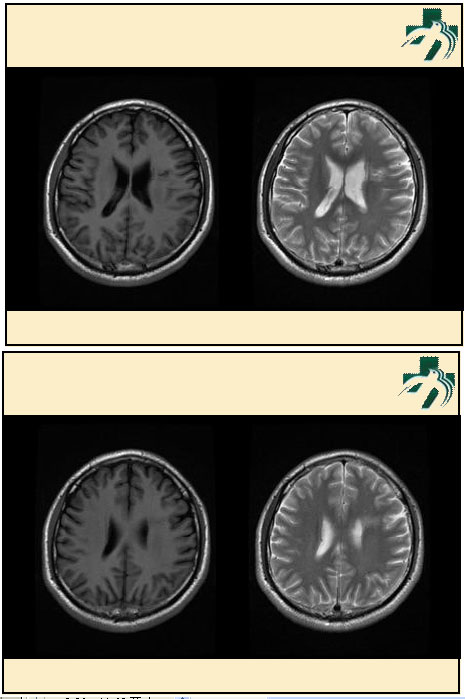

奴卡氏菌感染

第九期三博

读片会

病例之四

北京协和医院 提供

男性,22岁。自觉虫咬后皮疹、肢体麻木4月